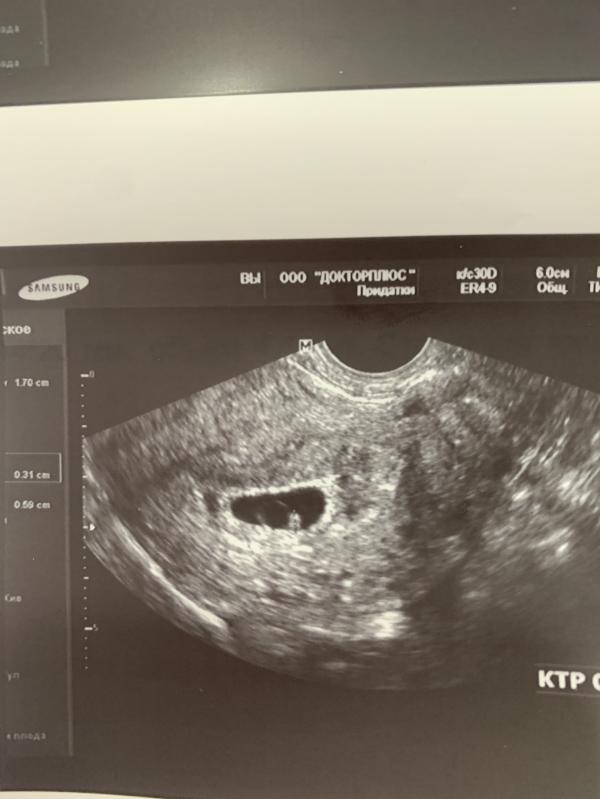

Сегодня была на втором узи , уже увидели эмбриончик, Сердцебиение было, но только мерцание посмотрели . Я успокоилась 🙏🏻🥹

По узи срок на неделю меньше .

По месячным срок кстати 6.3